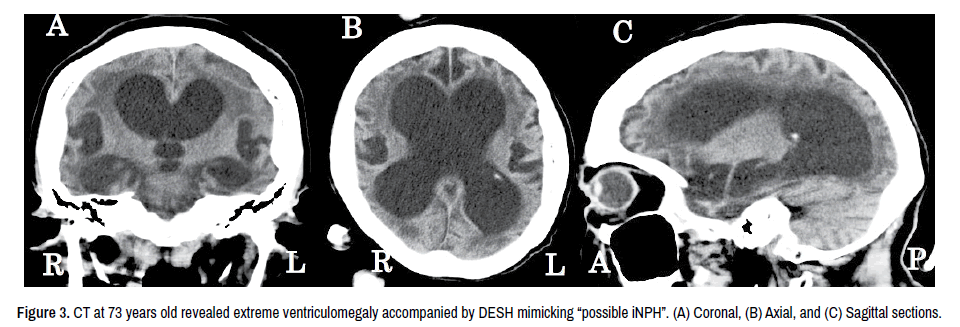

At 66-years-old, she was unable to walk and used a wheelchair every day. She spoke no meaningful sentences, often uttering such logoclonus as Ah-Ah-Ah- Ah. At 73 years old, she was admitted to Tokuyama Medical Association Hospital because of difficulty chewing and swallowing. Her speech was only logoclonus. She showed severe rigidity of all limbs, revealing contracted flexion postures at the elbows and knees. Intermittent myoclonus of a mild degree in both arms was seen. Laboratory data showed malnutrition (serum albumin 2.7 g/dl). Brain CT was performed instead of MRI because the latter seemed difficult to conduct due to the myoclonus of the arms. On brain CT, striking images of “possible iNPH” were noted, with remarkable ventriculomegaly associated with DESH according to the criteria of iNPH [9] (Figure 3). The oral intake of food was impossible, so percutaneous endoscopic gastrostomy (PEG) was performed.

neurological-disorders-extreme

Figure 3. CT at 73 years old revealed extreme ventriculomegaly accompanied by DESH mimicking “possible iNPH”. (A) Coronal, (B) Axial, and (C) Sagittal sections.